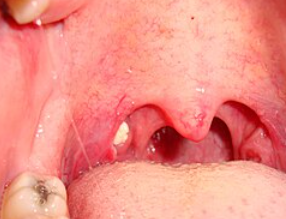

臭い玉スレ

女の子にもあると思うとえっちだよね

喉に出来るなら喉クソとか喉カスみたいな名前になりそうなのに

>粉瘤?

膿栓

くさたま!

13無念Nameとしあき26/03/15(日)16:53:23No.1394060012+

子供の頃に扁桃腺とアデノイド摘出してるから無い

15無念Nameとしあき26/03/15(日)16:53:55No.1394060126そうだねx12

>アリの巣にあげた

溝に入ってるから目視できるのは相当でかいやつだよ

18無念Nameとしあき26/03/15(日)16:57:19No.1394060946+

鼻風邪引くとめっちゃできる

鼻水が原料なのだろうか

扁桃腺が膿んだらその部分が腐って穴が開く

そこにらご飯の食べかすが入り込んで腐るから臭う

細菌やウイルスに食べカスとかだね

扁桃が細菌やウイルスを退治した後の死骸が扁桃の表面のくぼみにたまって塊になる

口呼吸による口の乾燥や慢性的な扁桃炎に慢性鼻炎なども出来やすい原因ではある